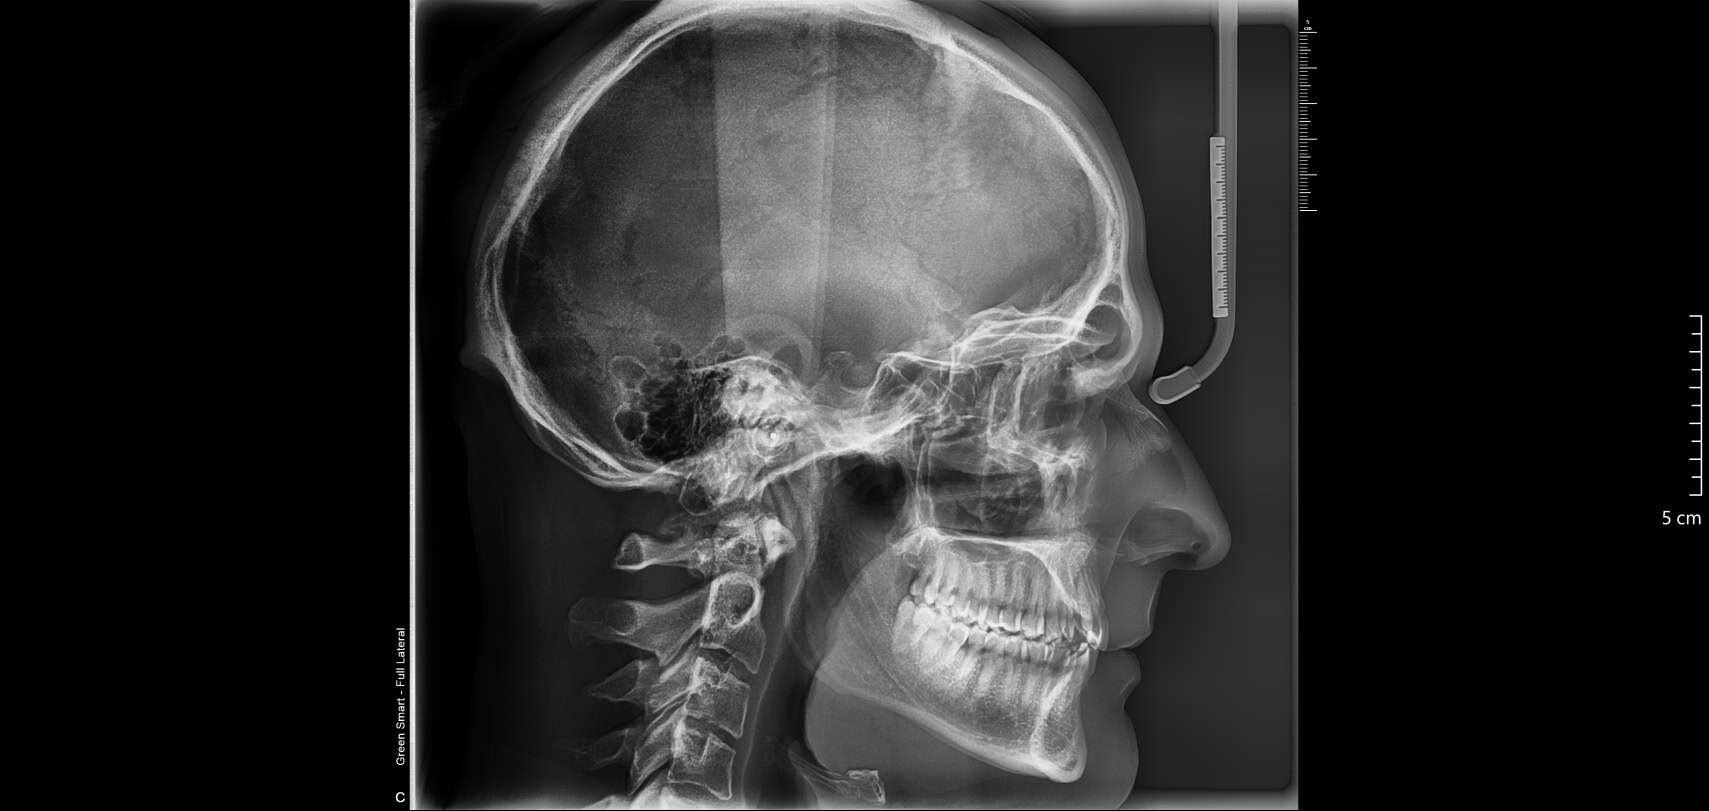

les télécrânes pour l'orthodontie: